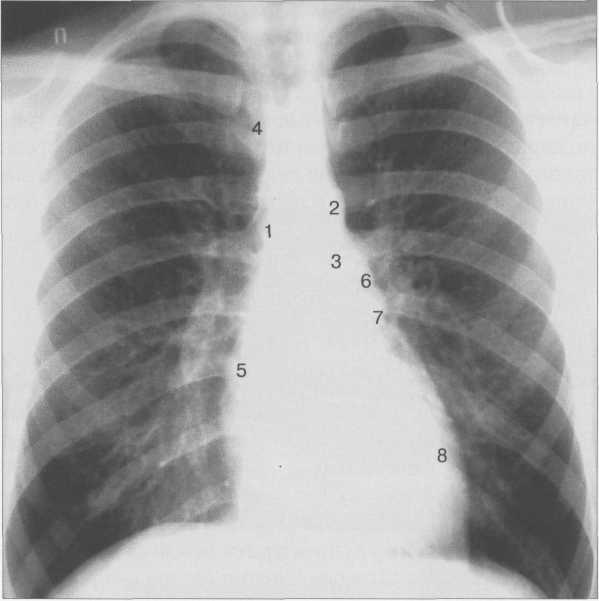

Рис. 9.24. Рентгенограмма грудной клетки. Передняя проекция.

1 — восходящая часть аорты; 2 — дуга аорты; 3 — нисходящая часть аорты; 4— верхняя полая вена; 5 — правое предсердие; 6 — легочный ствол; 7 — ушко левого предсердия; 8 — левый желудочек.

Состояние отдельных полостей сердца и крупных сосудов оценивается с помощью анализа краеобразующих дуг сердца (рис. 9.24).

Если сердце занимает косое положение, то ‘/3 его расположена справа, 2 /, — слева; расстояние от правого края позвоночника до наиболее удаленной точки правого контура сердца составляет 15—20 мм.

Правый контур образован двумя дугами: восходящая часть аорты и правое предсердие. Точка их пересечения носит название правого атриовазального угла. Протяженность первой и второй дуг должна быть одинаковой. У новорожденных правый желудочек имеет относительно большие размеры, поэтому протяженность второй дуги больше (см. рис. 9.22).

Левый контур образуют 4 дуги: дуга аорты, легочный ствол, ушко левого предсердия, левый желудочек. В детском возрасте (приблизительно до 7 лет) протяженность дуги легочного ствола преобладает над протяженностью дуги аорты, в дальнейшем протяженность дуг становится одинаковой. У подростков и людей астенического сложения дуга легочного ствола выпрямленная или выпуклая (см. рис. 9.23), у взрослых она, как правило, вогнутая. Левая граница сердца на уровне левого желудочка находится на уровне среднеключичной линии или на 1 см кнутри от нее.